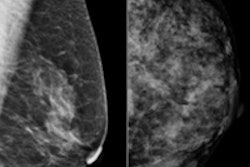

Initiated by Sen. Joe Simitian (D-Palo Alto), SB 1538 would require that following a mammogram, women with dense breast tissue are informed that dense breast tissue can obscure abnormalities on a mammogram, and that they may wish to discuss the potential value of additional screening with their doctor.